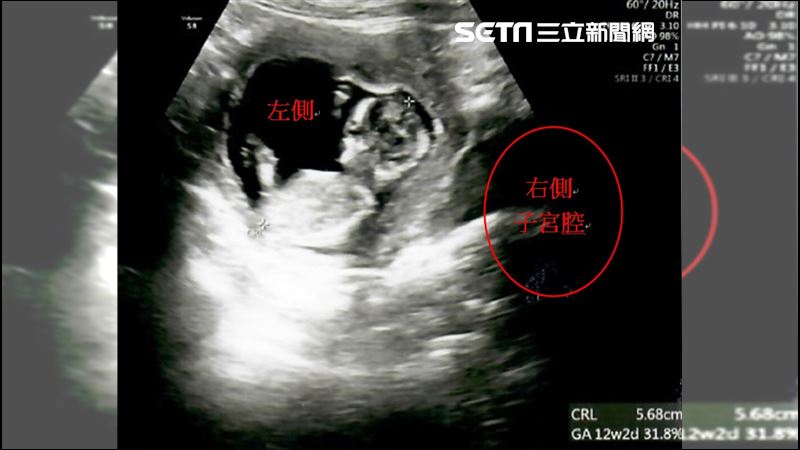

▲胚胎植入右側子宮腔的位置(圖/茂盛醫院提供)

因著求子心切,加上政府推出擴大試管補助方案,讓陳小姐和先生決定直接採用試管療程,不想再浪費時間嘗試自然受孕,希望能儘快抱到孩子。於是,李茂盛院長幫陳小姐進行1次取卵手術共取出9顆卵子,在受精後得到3顆囊胚,經過「AI人工智慧試管技術」、「胚胎影像即時監控系統(T/L)」(註1),從中找出發育最好的1顆第5天囊胚,植入右側的子宮腔內,囊胚即順利著床發育,直到孕期34週又2天時,陳小姐自然產下重達2460公克的健康男寶。